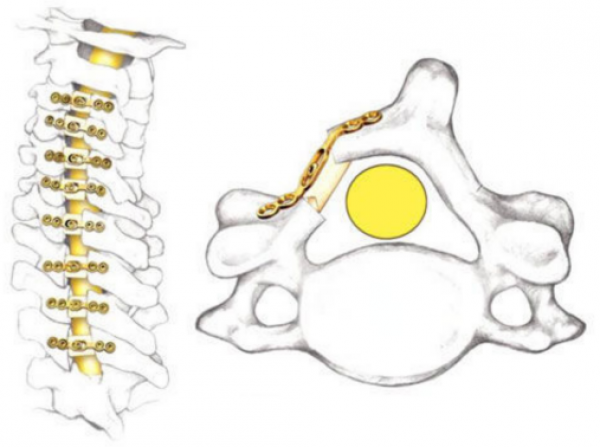

首先,我们要提到治疗颈椎管狭窄、颈椎后纵韧带骨化的经典术式——颈椎后路单开门椎管扩大成形术(ELAP)。因其脊髓功能改善明显、疗效持久等优点,已被骨科医师广泛应用于临床,然而有些患者在手术后出现了长期的颈项部及肩背部疼痛、僵硬,并伴酸胀、沉重感和肌肉痉挛,严重时甚至影响患工作与生活。1999年Kawaguchi首次将这种病态定义为轴性症状(AS)。

颈椎后路单开门椎管扩大成形术术后CT

常规后路单开门手术会对后方部分韧带复合体、双侧椎旁肌、部分棘突、棘间韧带、棘上韧带进行剥离或摘除,从而破坏维持颈椎生物力学的基本结构,影响颈椎结构的稳定性。故术后颈椎易发生生理曲度丢失,出现鹅颈畸形等并发症;另外由于手术创伤与组织缺损,术后发生广泛的结缔组织填充替代,出现广泛粘连,影响颈伸肌群功能及柔韧性。同时因肌肉附着点未重建,将导致不可恢复的肌肉萎缩,从而出现术后颈背部僵硬、酸胀、乏力、活动受限、活动受限等轴性症状。

后路椎管扩大成形术(ELAP)术后出现轴性症状的原因有很多:

①传统单开门椎管扩人成形术中采用关节囊悬吊法维持开门后的椎板位置,颈神经后支距离上关节突尖部仅5.5~7.4mm,丝线穿过关节囊时可以直接损伤脊神经后支。

②丝线有一定弹性,因术后颈椎的活动,悬吊的丝线对脊神经后支动态刺激或压迫,引起临床症状;

③如果显露时关节囊剥离太多,丝线只能缝在深层椎旁肌,术后坐起直立,伸肌收缩保持颈椎体位,丝线可牵拉引起伸肌痉挛、诱发颈背痛;

④电刀过度使用,静态牵拉引起肌肉坏死;

⑤未重建棘突上附着的肌群、术后伸肌无力。

但原因归结于底,不外乎这两方面:颈后路手术对颈椎后方神经肌肉的损伤和对颈椎生理活动的影响。